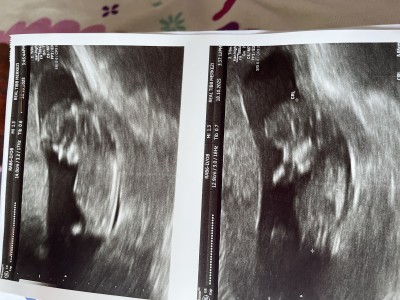

image

13 haftalık hamileyim bana da demedi , insan merakta ediyor

Tahmin etmedimi hic

Maalesef demedi şuan 14 haftalık oldum, bakalım gelecek kontrolde artık